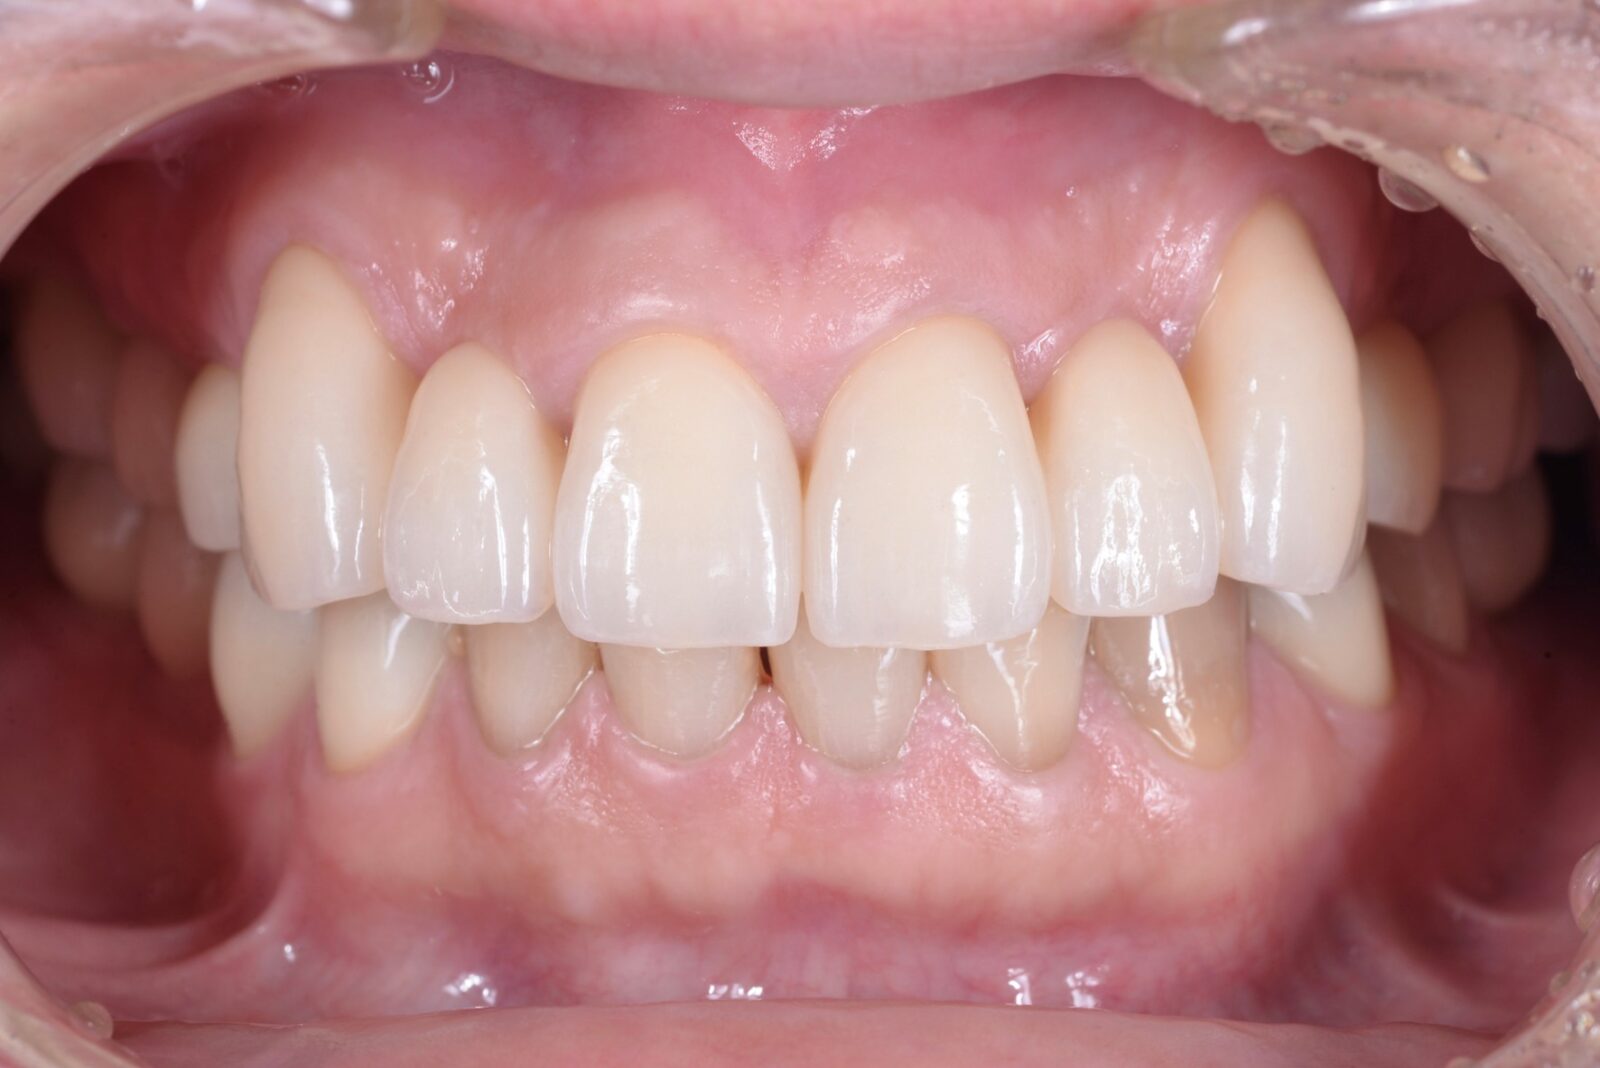

• 治療前

• 治療後